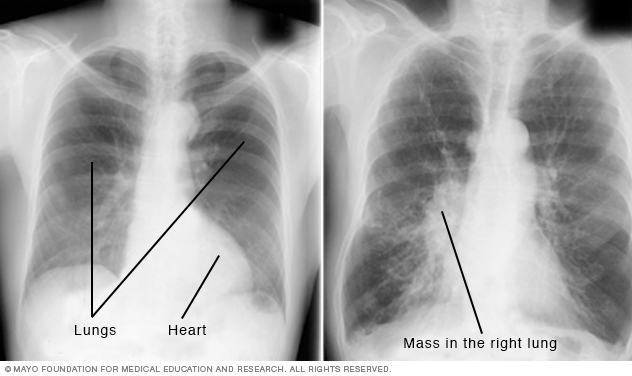

A chest X-ray helps detect problems with the heart and lungs. The chest X-ray on the left is typical. The image on the right shows a mass in the right lung.

Chest X-rays produce images of your heart, lungs, blood vessels, airways, and the bones of the chest and spine. Chest X-rays can also reveal fluid in or around your lungs or air surrounding a lung.